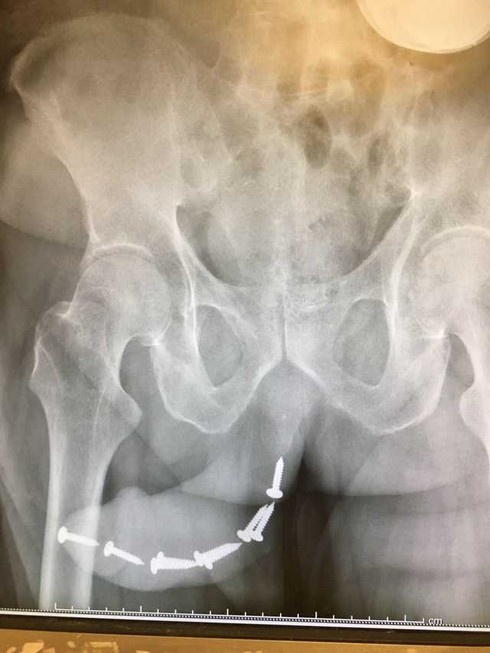

Khi tiếp nhận ca này, bác sĩ Dung cho biết bà cũng không khỏi sốc. Bệnh nhân trú ở Hà Nội, đến phòng khám trong tình trạng tiểu buốt. Khám không có nấm nhưng chảy máu ở đầu dương vật, bác sĩ chỉ định bệnh nhân đi chụp phim thì phát hiện hàng loạt chiếc đinh cấy bên trong.

Khai thác bệnh sử, người bệnh cho biết anh cấy hết lần này đến lần khác đinh vít vào vì mọi việc vẫn diễn ra trôi chảy cho đến gần đây mới xảy ra sự cố. Bệnh nhân được sang chuyên khoa Tiết niệu, gây mê và phẫu thuật gắp dị vật ra ngoài.

| Hình ảnh dương vật có nhiều đinh vít trên phim chụp. Ảnh: Infonet. |